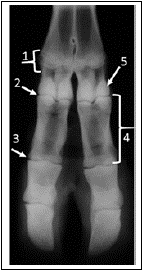

Analise a imagem a seguir.

As estruturas enumeradas sequencialmente de 1 a 5, no exame radiográfico do dígito de um bovino em exposição dorsopalmar, são: